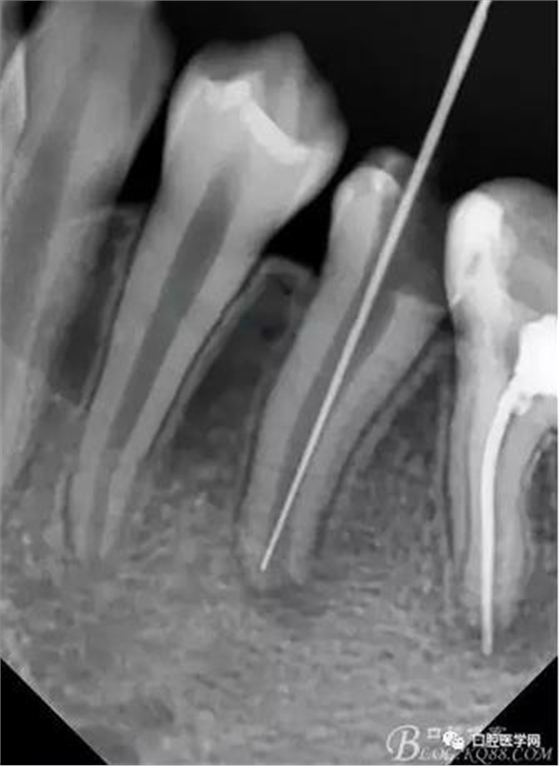

在拔髓的過程中遇到流血,但是不會(huì)疼,根管腔超級(jí)大,40#根管挫完全不用加壓就直接掉到根尖部,測(cè)長(zhǎng)直接報(bào)警,嚇了一跳,根尖孔這么大,40#根管挫很輕松就超出根尖孔。

擔(dān)心超出根尖孔破壞根尖組織,及時(shí)測(cè)長(zhǎng)再加一張X片,如下圖:

小心翼翼的控制根管長(zhǎng)度后進(jìn)行根管預(yù)備,3%雙氧水與生理鹽水交替沖洗,吸潮紙尖吸干,行氫氧化鈣根管充填,氧化鋅丁香油暫封,醫(yī)囑2周復(fù)診。